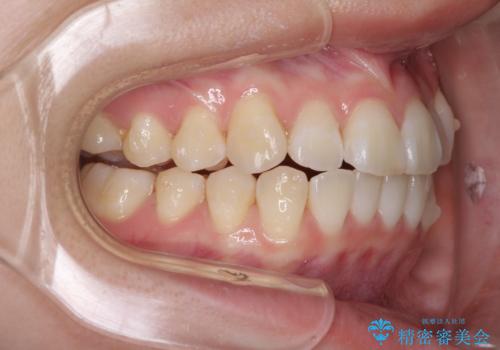

- 海外留学の予定があるが、学生のうちに歯列を整えたいとのことで来院された患者様です。

前歯にデコボコがあり、口元がやや突出した印象があったため、IPR(歯と歯の間を削る)と親知らずを抜歯した上での歯列全体の後方移動をメインに、インビザラインを用いて矯正治療を行うこととしました。

年に一度、夏休みの時期にしか帰国できないため、帰国のタイミングに合わせてマウスピース交換スケジュール治療計画としたため、3年半という期間を要しました。

留学先でもしっかりとマウスピースの装着を実践してくださったので、ご本人の満足のいく仕上がりとなりました。